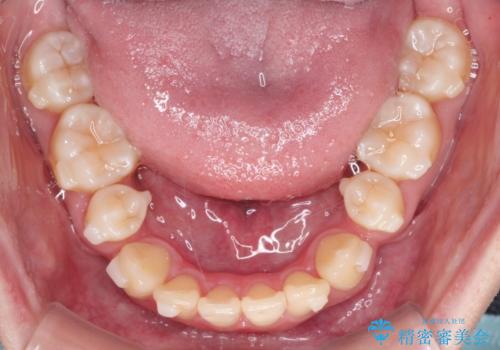

- 八重歯が気になるとのことでご相談いただきました。診察すると、歯列のスペース不足により犬歯が外側に飛び出している状態でした。このままでは歯を並べるスペースが足りないため、抜歯矯正が必要と判断。治療は目立ちにくいインビザラインで行い、歯の移動をサポートするためにゴムかけ(顎間ゴム)を併用する計画を立てました。

抜歯後、インビザラインを用いて少しずつ歯を移動させ、空いたスペースに八重歯を整列させました。さらに、ゴムかけを行うことで上下の噛み合わせを適切に調整。治療後は、八重歯が綺麗に並び、バランスの取れた歯並びと自然な噛み合わせを実現できました。患者様にも「仕上がりがとても綺麗で、口元の印象が変わった」とご満足いただきました。